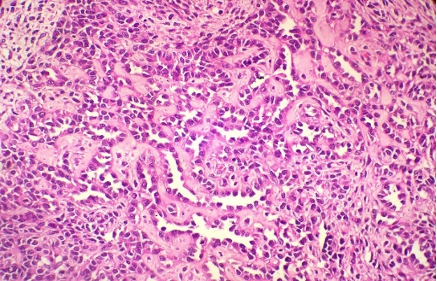

Section H and E x400. Mass in the wall of the small intestine in a 72 year old male patient who presented with frequent diarrhoea. Make you diagnosis.

Maltoma – small intestine- monocytoid B cells many showing plasmacytoid differentiation.